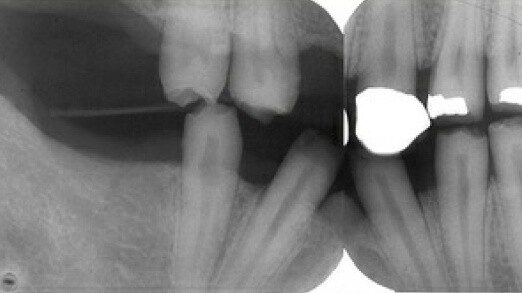

2 / 25

2. (Select ONE OR MORE correct answers)

The radiograph shows evidence of